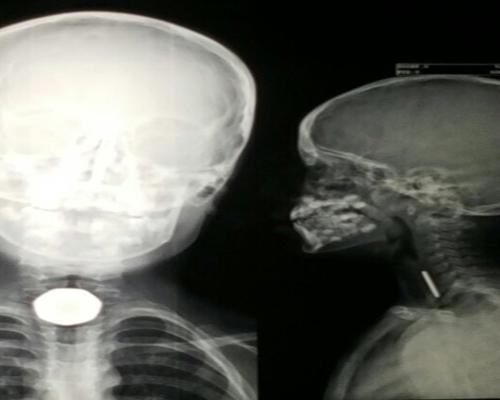

نجح فريق طبي في مستشفى الملك خالد العام بحفر الباطن في استخراج قطعة معدنية لطفل بعمر 7 سنوات من أعلى المريء باستخدام المنظار في عملية استغرقت 10 دقائق.

وأوضح الناطق الإعلامي لصحة حفر الباطن عبدالعزيز العنزي، أن الطفل حضر لطوارئ المستشفى وهو يشتكي من جسم غريب كان قد علق في أعلى المريء، مما تسبب في اختناق وعدم القدرة على البلع وغصة مع فرط باللعاب, عندها قرر الفريق الطبي إجراء العملية واتضح أنها قطعة معدنية , ونجحت العملية بدون حدوث مضاعفات، حيث غادر الطفل في اليوم التالي المستشفى وهو بصحة جيدة.